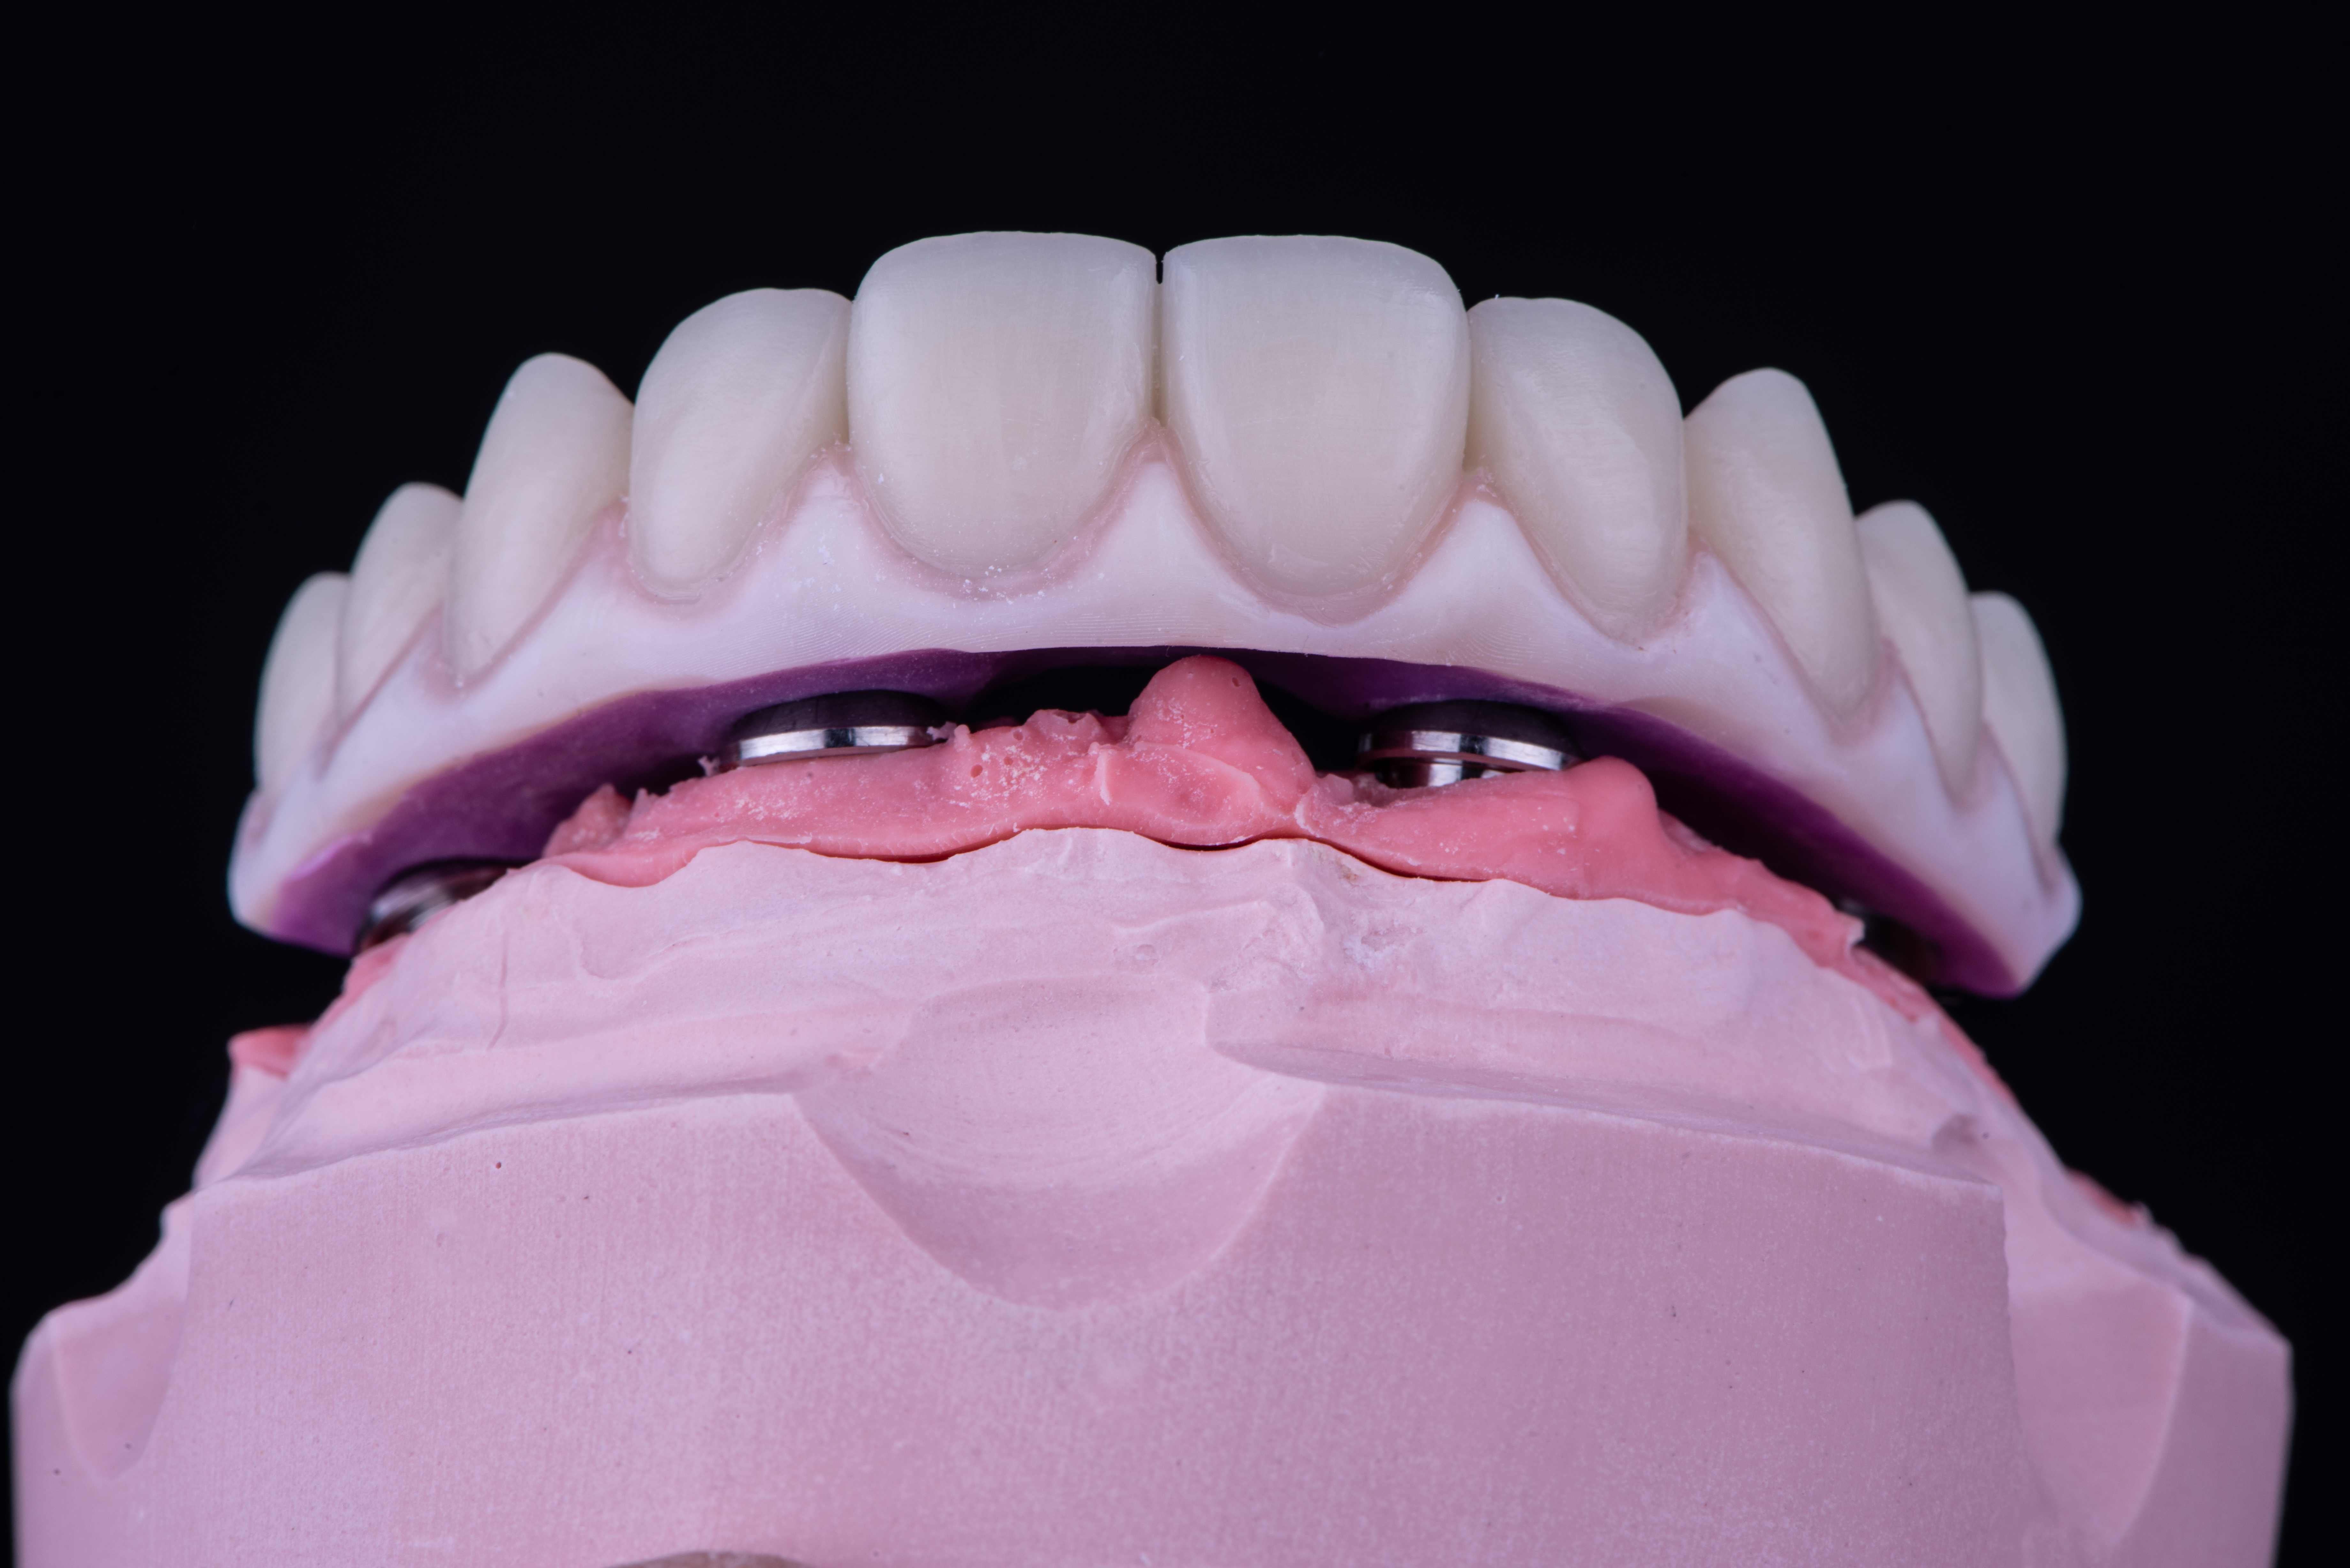

Le protesi definitive sono state infine prodotte in zirconia multilayer infiltrata la quale viene stratificata solo nella parte rosa (Fig. 20, 21, 22).

Fig. 20. Protesi definitive avvitate in zirconia monolitica stratificate solo nella componente rosa

Fig. 21. Protesi definitive avvitate in zirconia monolitica stratificate solo nella componente rosa